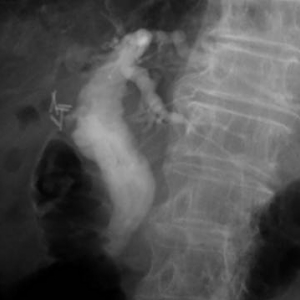

結石が胆管を閉塞し、胆管炎、閉塞性黄疸、急性膵炎などを発症します。緊急の処置が必要な場合が多く、放置すると命に係わる場合があります。通常バスケットカテーテルを用いて、結石を取り除きますが、石が大きい場合はESWL(体外衝撃波結石破砕術)を併用し排石する場合もあります。

ESWLとEST後large balloonによる乳頭拡張術を併用し完全排石に成功した巨大総胆管結石の一例